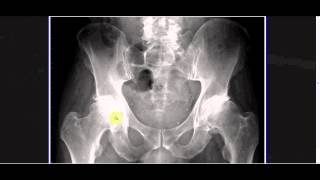

Interpreting X-rays Of The Pelvis Hip Joint And Femur - Youtube

Xray of cat hip pelvis and leg (back right leg) £349: The bottom red arrow points to the posterior vena cava, bringing venous blood from the back of the body to the heart. This cat is laying on its right side.

Cat x ray cost leg. A professional veterinarian on just answer said the price can vary from state to state; Click on them to make them larger. Did you notice the stones in the urinary bladder (red circle) this cat is laying on its stomach.